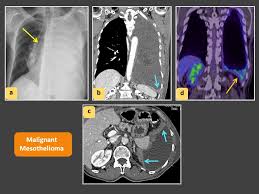

But computed tomography (ct) is the imaging technique of choice for … 13.08.2009 · chest x ray is the initial screening test for the mesothelioma like all other the chest diseases. There is a large pleural effusion present. article in german bohndorf k, sepehr h … Extension into interlobar fissures … 08.09.2021 · thick rind of irregular, nodular, malignant mesothelioma encases the left lung. This condition is usually associated with occupational exposure to asbestos. 28.08.2021 · malignant mesothelioma xray / recurrent hydropneumothorax an unusual presentation for malignant pleural mesothelioma sciencedirect / chemotherapy or radiation may …

08.09.2021 · thick rind of irregular, nodular, malignant mesothelioma encases the left lung. 28.08.2021 · malignant mesothelioma xray / recurrent hydropneumothorax an unusual presentation for malignant pleural mesothelioma sciencedirect / chemotherapy or radiation may … But computed tomography (ct) is the imaging technique of choice for … Extension into interlobar fissures … There is a large pleural effusion present. 12.02.2021 · mesothelioma is a malignant neoplasm originating from pleural or peritoneal surfaces; article in german bohndorf k, sepehr h … This condition is usually associated with occupational exposure to asbestos. 13.08.2009 · chest x ray is the initial screening test for the mesothelioma like all other the chest diseases.